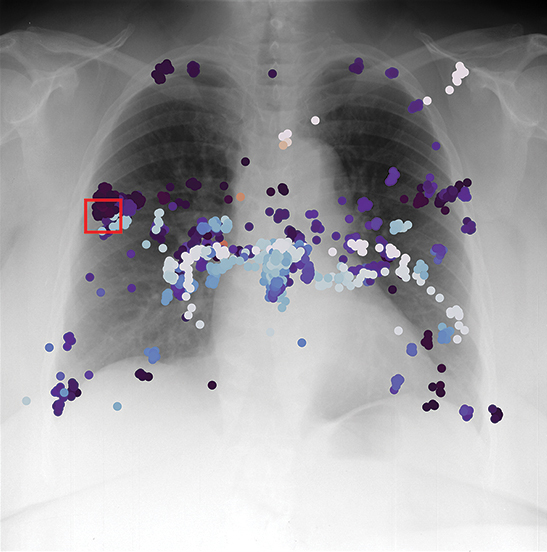

SwRI develops technology to support medical professionals, including an algorithm that identifies radiologist fatigue using gaze data. Colored spots represent gaze points, while the red square is the area that should receive the most attention.